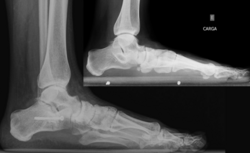

Для диагностики плоскостопия используют данные рентгенографии с рентгенометрией и плантографии при отпечатке подошвы стопы. По выраженности проявлений выделяют три степени продольного и четыре степени поперечного плоскостопия; продольное плоскостопие может сочетаться с любой степенью поперечного плоскостопия. Предварительный диагноз «плоскостопие» может быть выставлен ортопедом на основании физикального осмотра или анализа изображений, полученных при помощи подоскопа или плантографа. Определяются правильность расположения анатомических ориентиров стопы и голеностопного сустава, объём движений и углы отклонения стопы, реакция сводов и мышц на нагрузку, особенности походки, особенности износа обуви[4][2][3].

Другим методом диагностики продольного плоскостопия является измерение расстояния между бугристостью ладьевидной кости (костный выступ, находящийся ниже и спереди от медиальной лодыжки) и поверхностью опоры. Измерение проводят обычной сантиметровой линейкой в положении осматриваемого лица стоя. У взрослых мужчин это расстояние должно быть не менее четырёх сантиметров, у взрослых женщин не менее трёх сантиметров. Если соответствующие цифры ниже указанных границ, констатируется понижение продольного свода. Диагностика плоскостопия включает также анализ внешнего вида обуви пациента — при продольном плоскостопии происходит снашивание внутреннего края каблука и подошвы. Типичным проявлением симптоматического продольного плоскостопия является боль, зависящая от нагрузки, с возможной локализацией в средней части или во всей стопе. Продольное плоскостопие отрицательно влияет на всю биомеханику нижних конечностей, приводя к перегрузке медиальной группы мышц бедра, стабилизирующих голень, что проявляется энтезопатией «гусиной лапки» и в ряде случаев симптомами, сходными с клиническими проявлениями остеоартроза коленного сустава. Причиной типичных для продольного плоскостопия, но односторонних изменений, чаще всего является разница в длине ног (симптомы возникают на стороне более длинной ноги). Поперечное плоскостопие проявляется характерным внешним видом, а именно исчезновением поперечного свода и некоторыми другими объективными признаками[4][1].